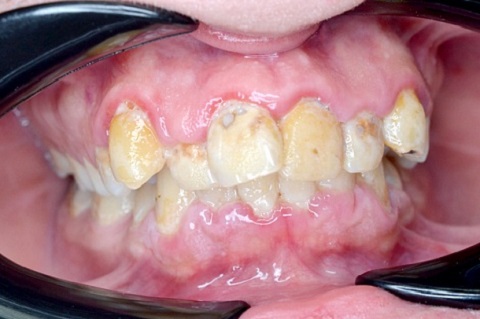

Пародонтит – популярное стоматологическое заболевание, которым поражено около 90% взрослого населения планеты. Так же, как и кариес, он приводит к потере зубов.

Пародонтит – это инфекционное воспаление пародонта. Чаще всего ему предшествует гингивит, при котором воспаляется поверхность десны. Появляются кровоточивость, дискомфортные ощущения. При пародонтите воспаление проникает глубже, симптомы могут усиливаться.

Если заболевание не лечить, оно переходит в пародонтоз, при котором разрушается костная ткань, и начинают выпадать зубы.